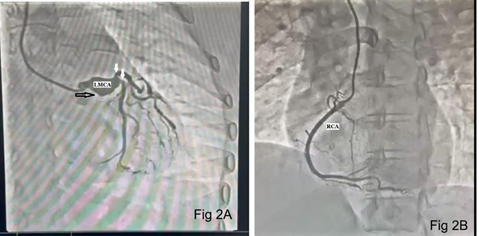

A 57-year-old female presented to our hospital with hypertension and unstable angina in July 2025. She has undergone coronary angiography and a failed attempt at PCI in the previous hospital. Her past records were unavailable. She denied any history of chest trauma, infection, pericarditis, or previous myocardial infection. On examination, she had a pulse of 65 beats/minute, a blood pressure of 160/90 mmHg, and a respiratory rate of 20 breaths/minute. Physical examination and laboratory tests were normal. Electrocardiography showed poor progression of ‘r’ waves in leads I and aVL, and T-wave inversion in the precordial leads (V1-V5, Fig 1). Transthoracic echocardiography showed akinetic mid anterior septum, mid anterior wall, and apex with an ejection fraction of 35%. Coronary angiography revealed a saccular aneurysm of the LMCA, measuring 20 mm x 26 mm. There was 90% stenosis of the LAD, 95% stenosis of the left circumflex artery, and a normal right coronary artery (Fig 2). In view of the LMCA aneurysm and double vessel CAD, the surgical option was considered. Intraoperative transesophageal echocardiography confirmed the presence of LMCA aneurysm (Fig 3A, 3B). Using cardiopulmonary bypass, the ascending aorta was opened and the LMCA aneurysm was oversewn and closed from its origin in the aortic sinus by 3-0 polypropylene pledgeted suture (Fig 3C). The proximal segment of the LAD was also aneurysmal, and it was ligated proximally and distally using pledgeted polypropylene suture (Fig 3D). The LAD and obtuse marginal artery were bypassed using vein grafts as conduits. The patients had an uneventful hospitalization and was discharged on the sixth postoperative day on dual antiplatelet therapy.

Figure 2: Coronary angiogram showing LMCA (left main coronary artery) aneurysm (black arrow) and stenoses of left anterior descending (LAD) and left circumflex artery (white arrows, Fig 2A). Normal right coronary artery (RCA, Fig 2B).